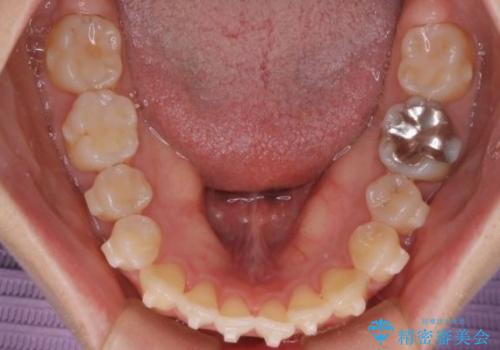

- 前歯のガタガタを主訴に来院された患者様です。

前歯の傾きも少し内側に入るように計画をたて、インビザラインにて治療を行いました。

このぐらいのガタガタであれば、インビザラインで簡単に治すことができます。